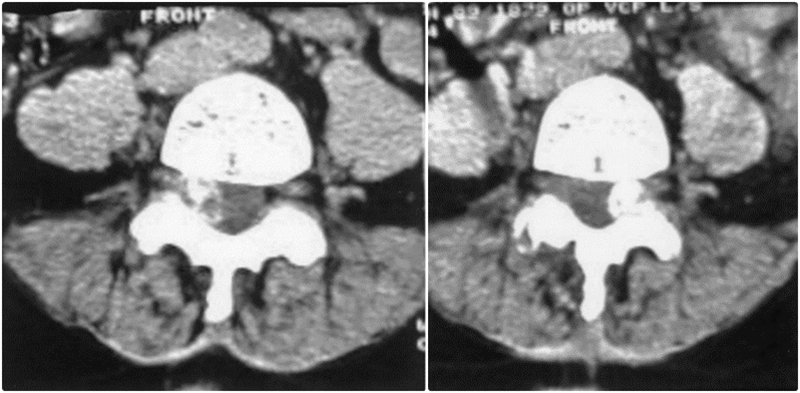

焦磷酸钙沉积疾病引起腰椎双侧症状性滑膜囊肿

CT扫描显示右侧与L4-L5关节突关节相关的钙化滑膜囊肿,明显侵犯椎管

A、注射钆前轴位T1加权MRI扫描显示硬膜囊背侧有低信号钙化肿块移位;B、注射钆后,低信号区周围可见强化环;C、矢状位T2加权MRI图像。箭头显示侧隐窝内有囊性肿块